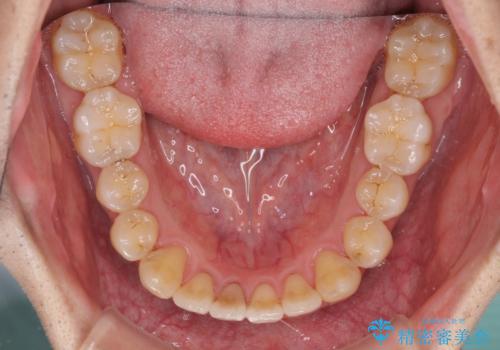

- 上下の前歯の反対咬合を気にして来院された患者様です。

インビザラインを用い、下顎はIPR(歯と歯の間を削る)と歯列全体を後方に移動させ、上顎は前歯を持ち上げることで、反対咬合を改善していくこととしました。

八重歯の歯根が見えている点も気になっているので、矯正歯科治療後に歯肉移植による根面被覆を行うこととしました。

矯正治療により元々気になっていた八重歯と、反対咬合が改善された歯の2本に対して根面被覆を行い、審美面の改善も達成しました。